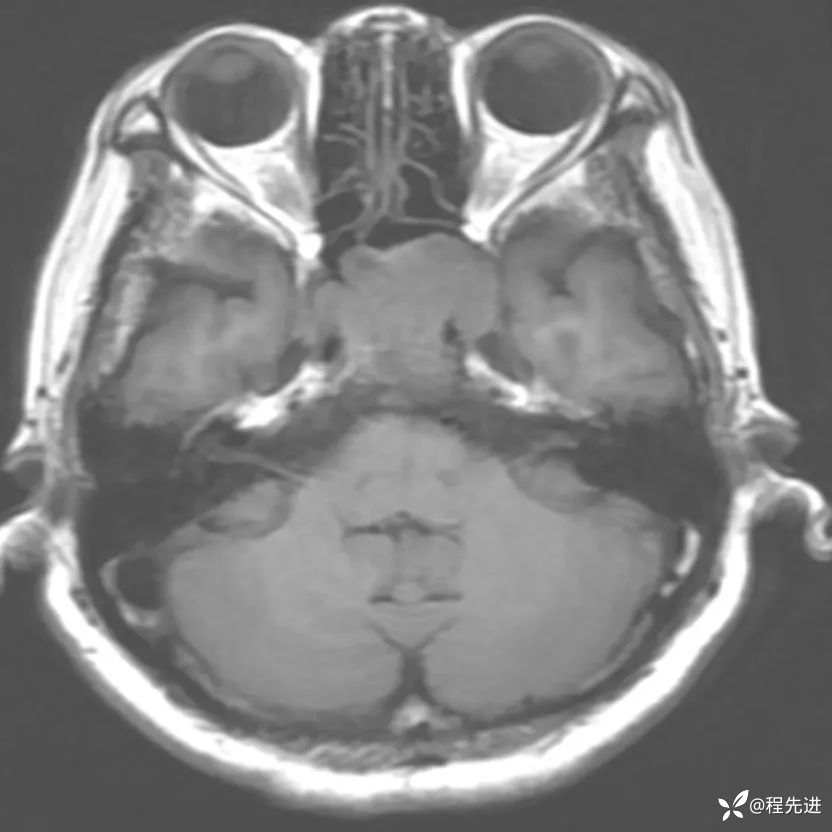

患者性别:女

患者年龄:63岁

简要病史:外伤检查发现颅底占位

MRI平扫+增强: